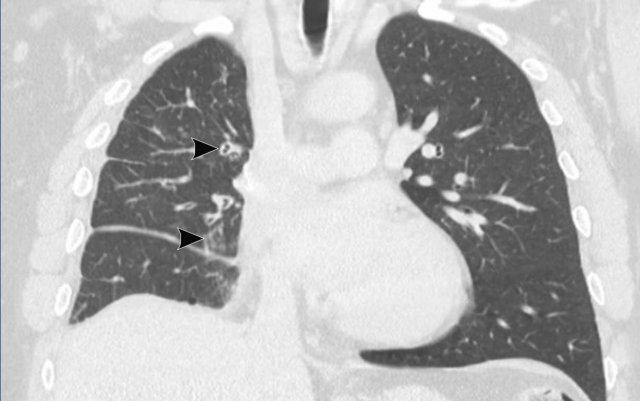

Bệnh u nhú khí-phế quản có tổn thương phổi ở bệnh nhân nam 54 tuổi, cho thấy hai u nhú trong lòng khí quản.

Tiếp tục xem trên cửa sổ phổi…

Hình ảnh cho thấy nhiều tổn thương dạng nang ở cả hai phổi (đầu mũi tên).

Trong một số ít trường hợp, tổn thương có thể lan rộng vào nhu mô phổi, biểu hiện là các nốt dạng nang thường gặp nhất ở các phân thùy đỉnh phụ thuộc trọng lực của thùy dưới. Có một nguy cơ nhỏ về biến đổi ác tính từ u nhú tế bào vảy thành ung thư biểu mô tế bào vảy.